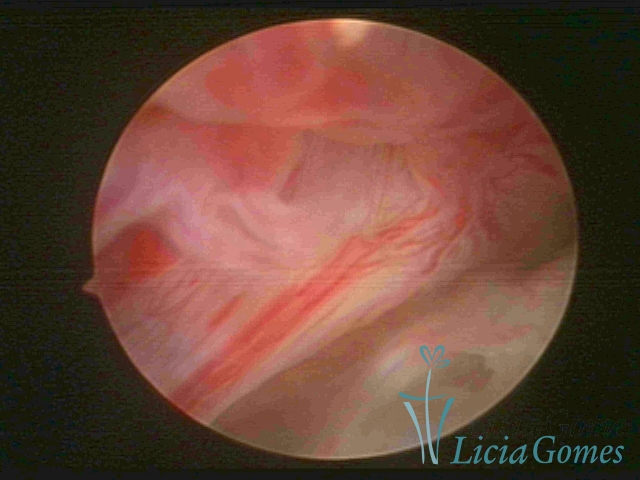

FIBROUS SYNECHIA

Uterine synechiae are scars (adherence) between the surface of the uterine walls, which may occur after the surgical procedure, uterine curettage, or after an inflammatory process in the uterine cavity (endometritis), which may lead to menstrual changes, infertility and obstetric complication such as abortion and premature birth.

• SINÉQUIA TIPO FIBROSA